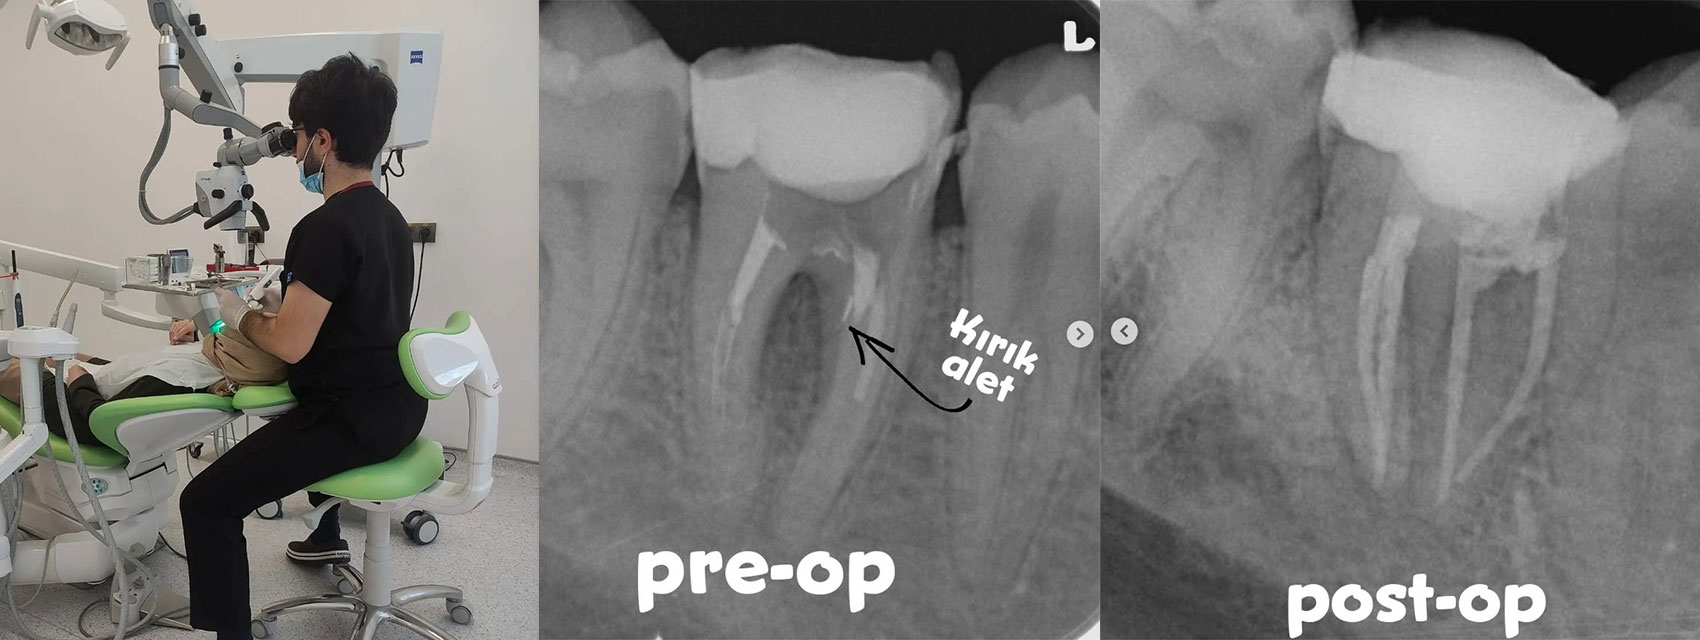

A 28-year-old healthy male patient was referred to our clinic from an external dental center.

Radiographic and clinical evaluation indicated that a previous retreatment attempt had been made, but the canal filling materials could not be removed.

During the previous procedure, a furcation perforation occurred and a separated instrument was observed in the mesial region.

• Under rubber dam isolation, the coronal restoration was removed, revealing the furcation perforation area.• The separated file fragment was removed using ultrasonic activation.